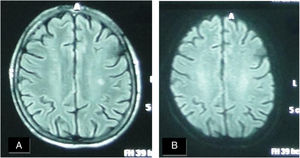

A female patient aged (60 years) and suffered from SS since (4 years). (A) FLAIR MRI shows multiple rather-defined hyperintense signal foci seen at deep periventricular white matter of both parietal regions with no comparable signal abnormality on DWI (B) suggesting late subacute to chronic ischemic lesions.

Six patients (40%) showed brain lesions using FLAIR MRI (in different supratentorial deep and subcortical brain regions (Table 2, Figs. 1 and 2). Three (20%) of them had severe peripheral vascular affection, while each of the remaining patients had mild, moderate or no peripheral vascular affection. Diffusion weighted MRI failed to detect any hypo- nor hyper-intense lesions (Table 2). A non-significant relation (P=.259) between the presence of WMH lesions and the severity of peripheral vascular affection of the disease (Medsgar Vascular Score) (Fig. 3), as well as non-significant strong correlation was found (r=0.085, P=.764) was also observed.